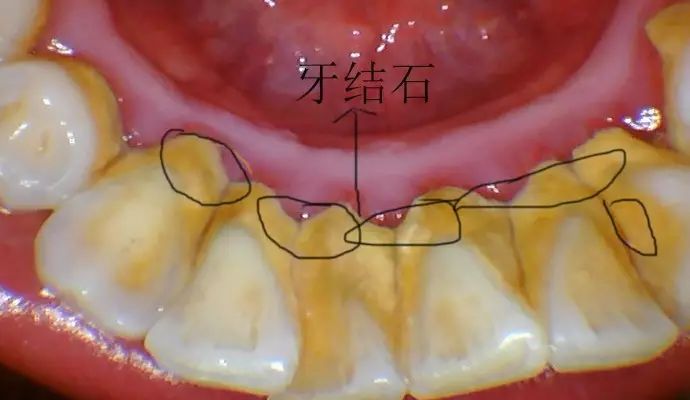

洗牙是一种通俗的说法,它的医学名称叫做龈上洁治术。是用器械从牙面上去除菌斑、牙石,并抛光牙面的一种治疗方法。在本文中,小编主要探讨目前最主流的超声波洁牙。

原因很简单,原来牙齿有藏污纳垢的牙石包裹,牙龈经常发炎、出血,牙骨质也可能被破坏了;洗掉牙石后,牙齿恢复原貌,但由于牙龈退缩,导致牙根位置的牙本质暴露出来,一碰到冷热酸甜,就会让人酸软不适。

①限制摄入可刺激牙齿敏感的食物和饮料,包括碳酸饮料、酸果汁等,因为这些食物可溶解牙齿表面的玷污层,导致牙本质小管开放,加重牙本质敏感。 ②吃酸性食物后不应该立即刷牙,以免酸蚀和磨耗综合作用于牙齿,加速牙体组织的损坏。 ③对于持续牙本质敏感的人,可以尝试含有钾离子的抗敏牙膏,因为钾离子可以使牙髓神经去极化,缓解牙本质敏感。 ④如果还没有解决问题,可以去看牙医,必要时做脱敏治疗或其他处理。 如何防止洗牙后牙齿酸软? 1、洁牙前使用脱敏牙膏 洁牙时引起“酸软感”主要是由于牙齿敏感引起。建议在洁牙前4-10天使用有脱敏效果的牙膏,这样能减轻洁牙时的酸软感。在洁牙后仍可继续使用,以减轻洁牙后的酸软感。 2、洁牙前进行药物消炎治疗 洁牙时引起“疼痛感”主要是由于牙龈有急性炎症引起。在洁牙前,应先检查牙龈是否处于急性炎症期,若处于急性炎症期,则先要进行全身或局部的药物消炎治疗,再做洁牙。 3、分次洁牙 对于牙结石较多较厚、药物抗炎效果欠佳或脱敏治疗欠佳的患者,做一次对这些患者来说,太辛苦,而分几次洁牙,“化整为零”,患者容易接受,而且在洁牙间期,还可继续进行抗炎治疗或脱敏治疗,这可大大减轻酸痛感。 4、定期洁牙 长年累积的牙结石又多又硬,以致洁牙时需加大洁牙机的强度才能去除,这样会加重牙齿酸痛感。半年、一年或两年定期洁牙,在牙结石小的时候,形成的量不多,质较松,很容易去除,这样定期洁牙,就不易造成洁牙时的酸痛感。 洗牙后,牙缝会变大吗? 其实这是一种感觉上的错觉。 洗牙后之所以让人容易有牙缝变大的感觉,是因为在洗牙的过程中,把堆积在牙龈表面、牙缝间的牙结石通过超声波震动方式震碎、清除,而使得舌头在碰触牙齿时,不再受到牙结石干扰,可直接碰触牙缝所致。其实,这些牙缝是本身早已存在的,与洗牙并无关。 洗牙后,牙齿会脏得更快吗? 洗牙后牙齿会不会变脏,主要还是在于个人维护。就像牙菌斑会不断再生,但是我们不能因为它而去否定洗牙,难道有了蛀牙,我们就不刷牙了吗?道理是一样的,不要随便否定一个事物的价值,做好自己应该做的就好。 不想牙齿变脏,平时刷牙是必不可少的一项工作,还有一个很重要的就是,坚持定期洗牙,比如每隔半年洗一次牙,加上平时刷牙,牙齿基本就能一直保持洁净,口腔卫生也会大大转好。 哪些人不适宜洁牙?